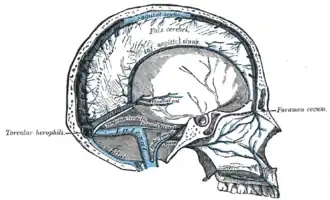

Sagittal section of the skull, showing the sinuses of the dura.

Sagittal section of the skull, showing the sinuses of the dura. -

The sinuses at the base of the skull.

The sinuses at the base of the skull. -